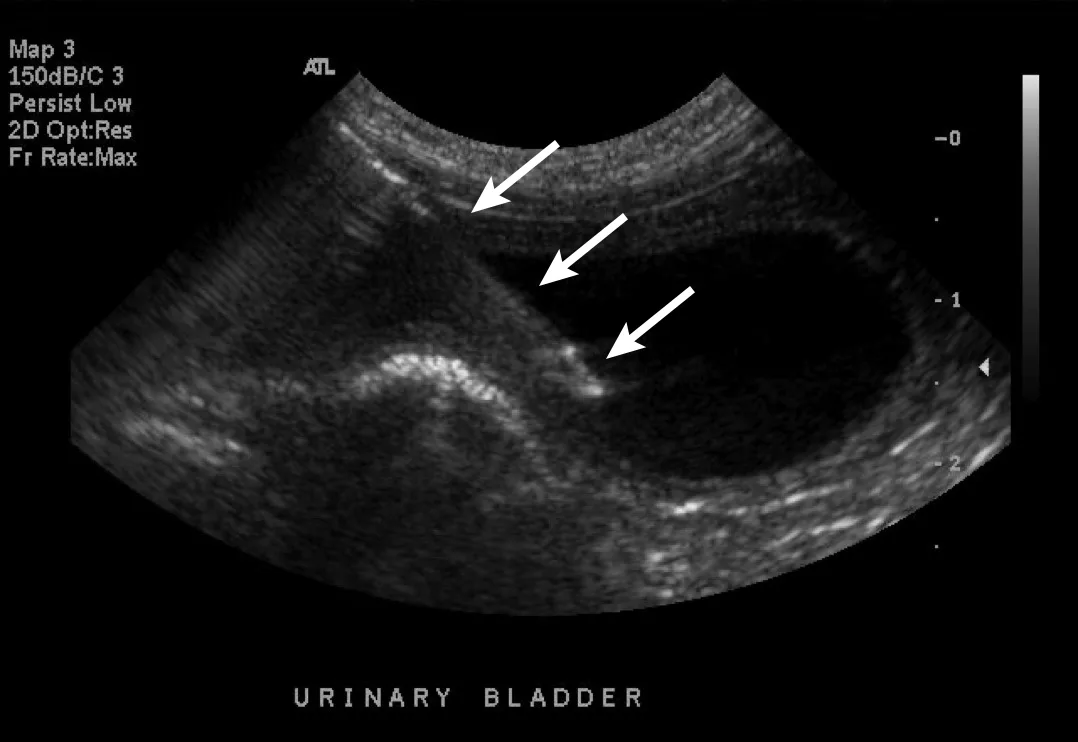

Cystitis is generally a diagnosis of exclusion, especially in cats with hematuria or difficulty urinating (ie, stranguria). Sterile and bacterial cystitis cannot be differentiated on ultrasound, and cystocentesis is needed to further characterize sediment even if hyperechoic foci are identified. The urinary bladder wall may be mildly thick or irregular on the luminal side (Figure 1). When measuring the wall of the urinary bladder, a representative region should be selected and the measurement made from the bladder mucosa to the serosa layer. Care should be taken to remain perpendicular to the wall, not to the ultrasound probe, to minimize measurement enlargement that can occur with obliquity. Overall measurement is more important for repeat evaluation to determine whether the urinary bladder is increasing or decreasing in size; retaining a consistent amount of urine (or catheterizing the patient and adding sterile saline) can help ensure consistent measurements.

Sagittal image of the urinary bladder with a diffusely thick wall due to cystitis. Left, cranial; bottom, dorsal